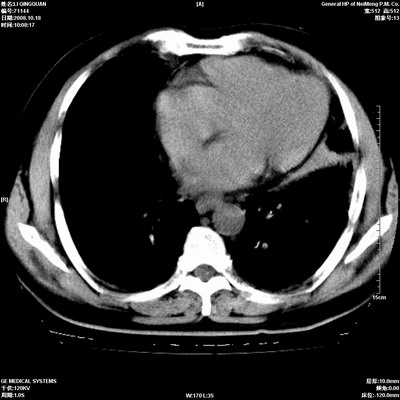

以下是引用duguo在2008-10-19 13:59:00的发言:[br]左肺上叶支气管狭窄,首先考虑中心型肺癌伴阻塞性肺炎\\肺不张.

以下是引用ybing在2008-10-19 12:58:00的发言:[br]左肺上叶阻塞性炎症-建议支气管镜进一步检查除外中央型肺癌

以下是引用随光逐影在2008-10-19 14:31:00的发言:[br]考虑左肺中央型肺癌并左肺上叶阻塞性肺炎,肺不张。